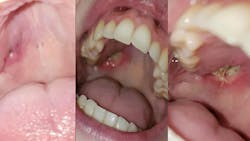

Symptoms include sinus pain, nasal discharge, frequent nosebleeds, nasal ulcerations, and inflammation in the ear. Orofacial and oral manifestations include “strawberry-like” gingival enlargement, facial paralysis, parotitis (inflammation in the parotid glands), perforation of the palate, and ulcers that affect the buccal and lingual mucosa as well as the tonsils and floor of the mouth.4 These lesions can present for long periods of time before multiple organs are involved.3 It is important as clinicians to be aware of these symptoms as they can be the initial signs in someone with granulomatosis with polyangiitis, and can be a crucial aspect of their diagnosis. To receive a definitive diagnosis, positive biopsies and a positive test for the antineutrophil cytoplasmic antibody (ANCA) blood test are necessary.3

As dental hygienists, it’s important to be aware of the clinical signs and symptoms of granulomatosis with polyangiitis, as well as any other condition. See figure 1 for recent examples of a granulomatosis with polyangiitis patient who is only 24 years old. Although my mother-in-law never presented with any oral lesions, we should be aware of these symptoms because an early diagnosis could determine a patient’s prognosis. Due to the high prednisone treatments, the risk of becoming immunosuppressed is increased, and this can greatly affect the gingival tissue and a patient’s healing process. This is one of the many reasons we should attain a medical history and medication update at every dental visit. Educating and encouraging patients to practice good oral hygiene is extremely important to their oral and systemic health.